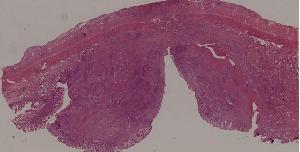

77. Chronic pyelonephritis